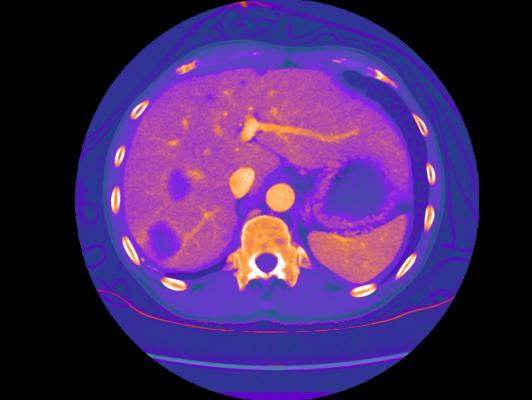

GSI Xtream on Revolution CT is the first volume spectral CT technology designed to improve small lesion detection, tissue characterization and metal artifact reduction, with a simplified workflow.

Spectral CT allows clinicians to go beyond anatomy visualization to tissue characterization, allowing for differentiation between similar HU densities such as cysts and enhancing lesions. With a contrast-to-noise ratio 60 percent higher at 120 kV than single energy CT, monochromatic images improve lesion detection and enhance contrast. Bhavik Patel, M.D., assistant professor of radiology, Duke Medical Center, said “By using GSI, we may be able to characterize a lesion for diagnosis from one exam, which could generate cost savings and add value – both clinically for the patient and economically for the health system.”

GSI Xtream enhances Revolution CT’s platform with wide collimation and 50 cm field-of-view (FOV) to deliver the only volume spectral CT. Enabled by ultrafast kV switching, clinicians can scan more challenging patients and reduce the effects of motion. The Gemstone Clarity detector combined with ASiR-V delivers dose neutral exams for patients of any size.